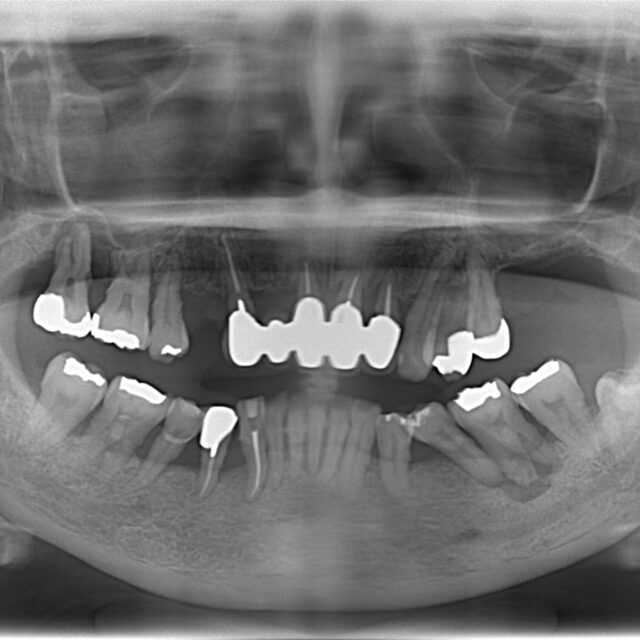

歯周病